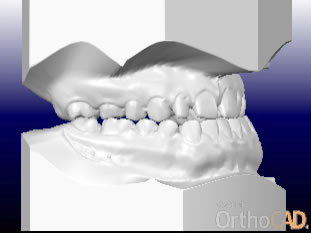

さまざまな問題をふくんでいたので、最新のCAD技術を応用した矯正治療分析ソフトを用いて治療計画を立てて、動画で治療経過予測を説明しています。

こちらに示しているのは治療開始時、手術直前予測、手術後予測の3段階静止画像ですが、実際のCADでは治療経過を動画で表現しています。

右横から見た

治療前、手術前、手術後の予測CAD

(表示を歯だけにして、前歯の変化をわかりやすくしました)